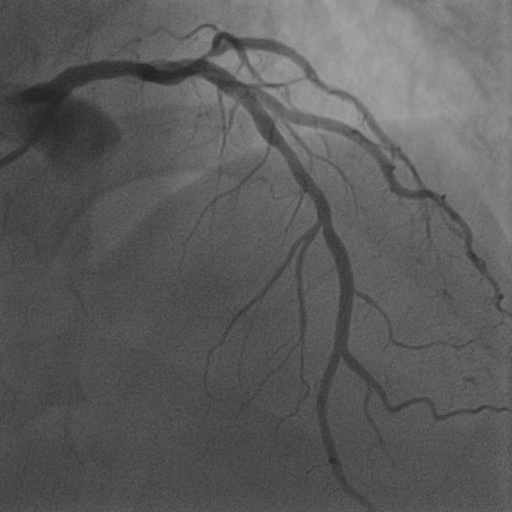

4.1 XACV Dataset

We collect 111 complete records of coronary artery X-ray videos, encompassing the injection, flow through the blood vessels around the heart, and dissipation of the contrast agent. Subsequently, we establish the XACV (X-ray Angiography Coronary Video) dataset. Each video consists of varying numbers of high-resolution coronary artery X-ray images. We invite experienced radiologists to annotate the vascular regions, focusing on one or two frames where the contrast agent is most prominent in each video. The XCAD dataset contains only a single image, and the CADICA video dataset does not provide corresponding ground truth. Therefore, in the following experiments, we conduct all the analyses on our collected XACV dataset and the corresponding GT for each sequence. In Figure 5, we show that compared to other publicly available datasets, XCAD [33] and CADICA [19], our dataset exhibits finer annotations in the vascular regions, providing an advantage for future related tasks. The development and use of our dataset have been approved by our institution’s IRB.

We also provide visual comparison results in Figure 6, demonstrating our vessel segmentation results are more accurate, complete, and closer to the ground truth masks. Moreover, in some sequences, our method even performs on par with supervised U-Net [48], as U-Net might face an overfitting problem with insufficient training data. Additionally, we provide visual comparisons on the CADICA [19] dataset, which is also a coronary artery X-ray video dataset but without ground truth labeling. Figure 7 demonstrates that our test-time training scheme generalizes better than existing methods. Due to the space limit, we provide more visual comparisons in the appendix.